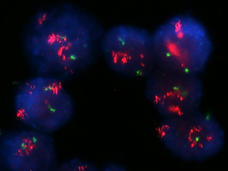

Brain Cancer Cells Hijack Gene “On Switches” to Drive Tumor Growth

Glioblastoma cells sneak many copies of a key oncogene into circular pieces of DNA. In a new NCI-funded study, scientists found that the cells also slip several different genetic “on switches” into these DNA circles, helping to fuel the cancer’s growth.